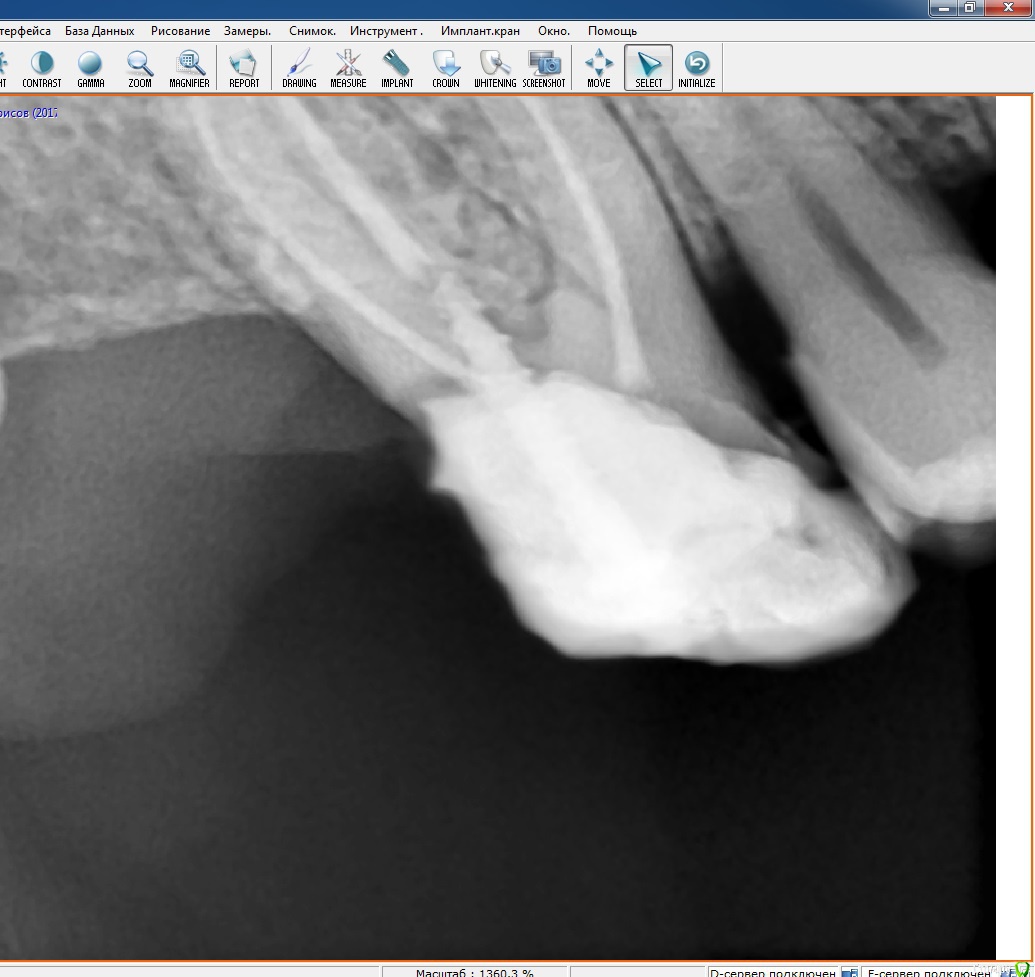

RuStom Опубликовано 8 июня, 2016 Автор Поделиться Опубликовано 8 июня, 2016 (изменено) Вот опять случай. Пришел пациент от терапевта. Зуб надо спасать. Снял пломбу, при снятии зацепил десну, все кровит. коффер даже не пытался наложить в данном случае.Имеем такую картину. На фото не совсем понятно, не чувствуется объема. Но над краем зуба миллиметра 1,5 стеночка из десны. Само "ложе для вкладки" сейчас имеет чашеобразную форму. Т.е стенки кверху становятся тоньше.Темное на фото - это я прикладывал Вискостат. Т.е чтобы сделать надежную конструкцию - мне нужно иссечь десну на уровень с корнем (а то и глубже, т.к на нынешнем уровне стенки тонкие), плюс заглубиться милиметра на 1,5, чтобы создать уступ и феррул. При этом "десна уйдет" и у 5 зуба. Как надежнее сделать? http://s33.postimg.org/8lu64zcfj/DSC_9233.jpg Изменено 8 июня, 2016 пользователем RuStom Ссылка на комментарий

Витторио Орлионе Опубликовано 17 января, 2017 Поделиться Опубликовано 17 января, 2017 (изменено) а что скажете про такой случай?! Быть удалению или не быть?!? Изменено 17 января, 2017 пользователем Витторио Орлионе Ссылка на комментарий

krokomot Опубликовано 17 января, 2017 Поделиться Опубликовано 17 января, 2017 а что скажете про такой случай?! Быть удалению или не быть?!?удаление, фуркация поражена Ссылка на комментарий

chervoncevdaniil Опубликовано 17 января, 2017 Поделиться Опубликовано 17 января, 2017 Удалять Ссылка на комментарий

Витторио Орлионе Опубликовано 17 января, 2017 Поделиться Опубликовано 17 января, 2017 (изменено) Вот он Изменено 17 января, 2017 пользователем Витторио Орлионе Ссылка на комментарий